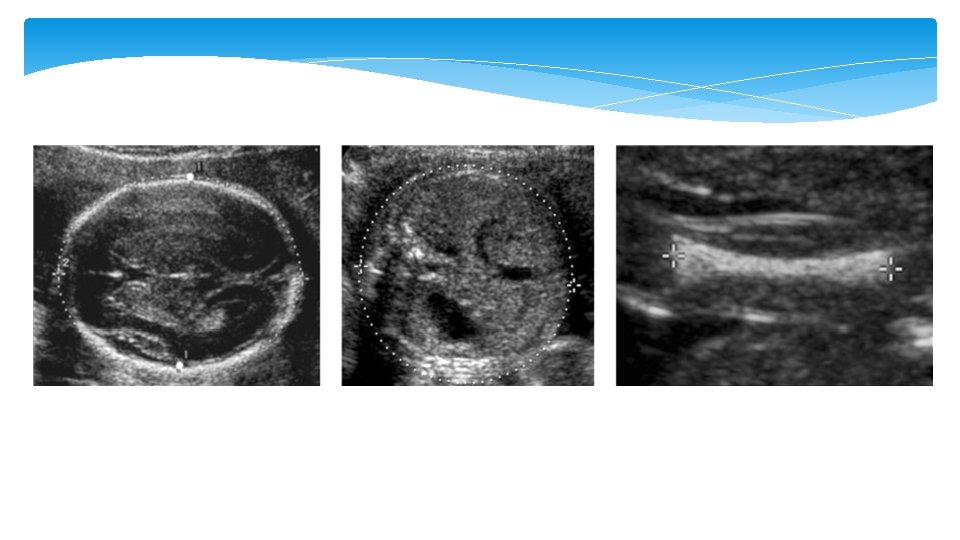

Increased Nuchal fold The most sensitive (40 to 50 percent) and specific (99 percent) single ultrasound marker for Down syndrome in the second trimester (15 to 20 weeks but not later) An increased nuchal fold is detected in 20 to 33 percent of fetuses with Down syndrome and 0. 5 to 2 percent of euploid fetuses Measurement between the outer edge of the occipital bone to the outer margin of the skin and is taken in the axial plane

Mild ventriculomegaly Ventriculomegaly is a condition caused when there is dilated atrium beyond 10 mm. The mild ventriculomegaly (MVM), or what is called borderline ventriculomegaly, range between 10 – 12 mm and 10– 15 mm. It can be an isolated finding or be associated with an underlying cranial defect or anomaly such as agenesis of the corpus callosum

Renal Pyelectasis Mild pyelectasis refers to dilatation of the renal pelvis >4– 5 mm and <10 mm in the antero-posterior diameter measured in transverse section of the fetal abdomen. The cut-off value which is most frequently used in this dimesion is >4 mm in the 2 nd trimester and >7 mm thereafter